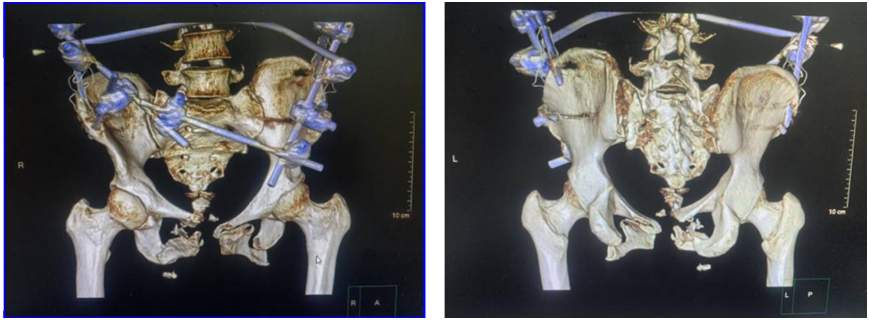

术前三维CT显示:骨盆耻骨上下支粉碎性骨折伴耻骨联合脱位,右侧骶髂关节脱位。

病情平稳后,副院长、主任医师孙涛会同创伤中心医疗团队进行病例讨论,大家一致认为:鉴于患者骨盆骨折的类型,可实施骨盆后环闭合牵引复位,在骨科机器人导航下行创伤小、出血少的骶髂螺钉固定术;患者骨盆前环损伤严重,双侧耻骨上下支粉碎性骨折伴耻骨联合分离,可通过Stoppa入路,完成双侧耻骨及耻骨联合的复位及钢板固定。

术中通过机器人导航规划骶1及骶2两枚骶髂螺钉。